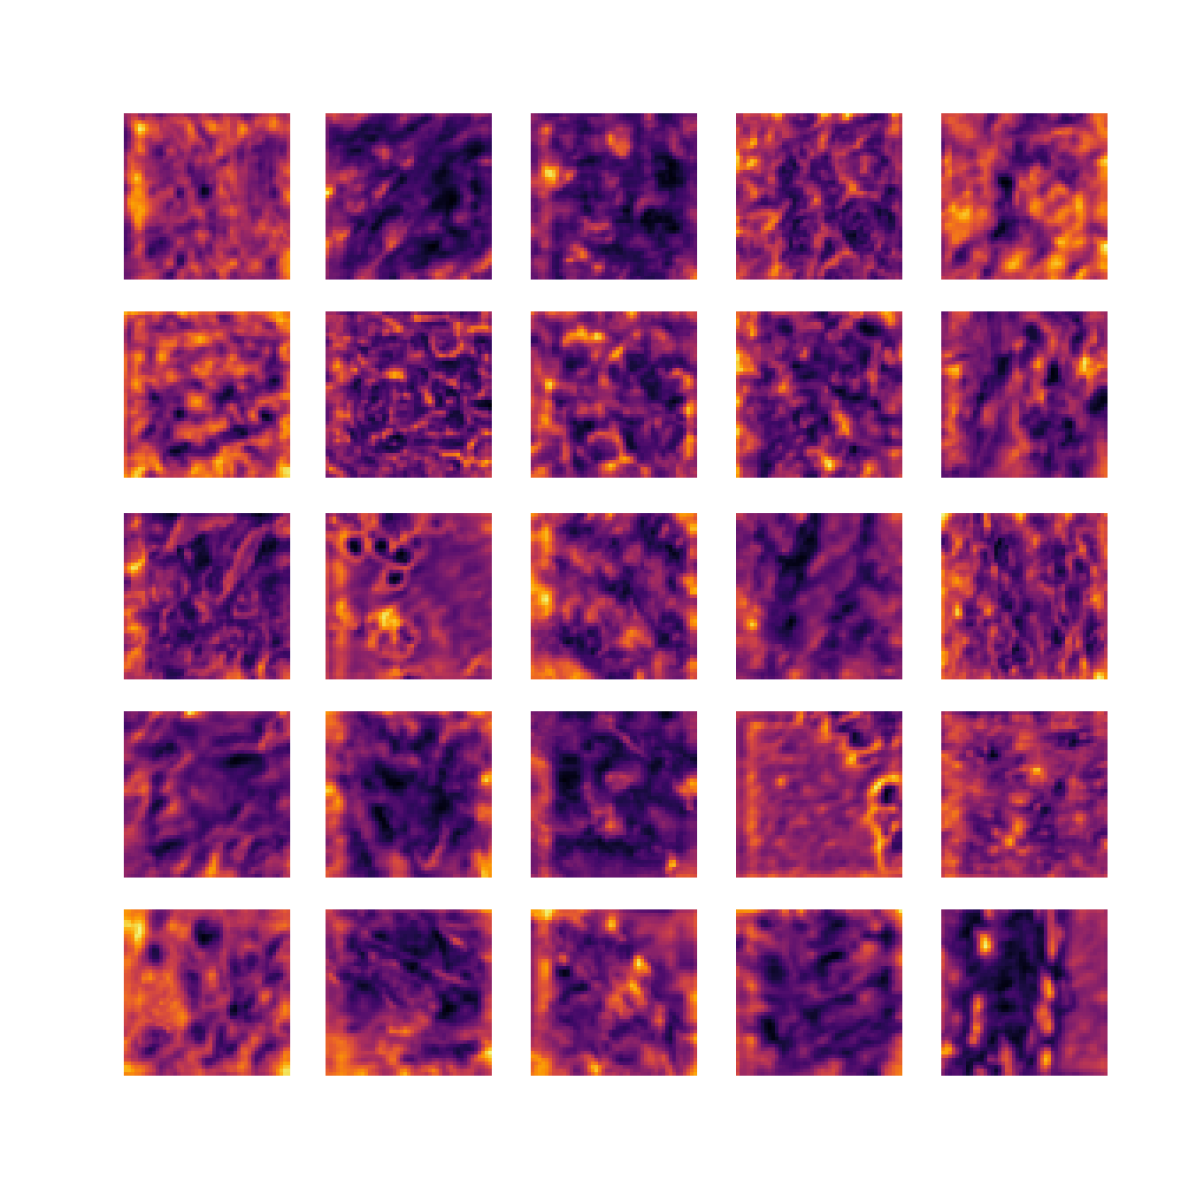

We also analyse the activation maps for each model using GradCAM as described in section S3. This offers more insight into the areas of the image which are contributing most heavily to the models’ representations. In Figure 4(b) we present some representative examples, however, a larger selection which was chosen at random is presented in Figures S10 to S25. The larger selection makes it easier to see the emergent patterns, including that privileged Siamese models tend to mainly identify features which are strongly present in both inputs, while unprivileged Siamese models tend to learn more diffuse features that are not specific to one cell phenotype or image region. TriDeNT ♆ incorporates both sets of features, learning both features specific to the privileged data and more the general features associated with unprivileged Siamese networks.

We can see in Figure 4(b) panel A that for ERG, the privileged Siamese model focuses almost exclusively on any nuclei which could be endothelial cells. As there are very few endothelial cells in the dataset, it could be an effective strategy to identify anything that could potentially be an endothelial cell to minimise the difference between the representations of the H&E model and the IF mask model. In the corresponding unprivileged Siamese image, we see that the model identifies some of these nuclei, albeit less strongly, but also focuses heavily on the other tissue and even the background, while strongly fixating on two spots of debris in the center of the image. This model has less ‘incentive’ to learn the weak features related to endothelial cells as these occur rarely and are not easy to detect, while more generic strong features such as the presence of connective tissue and the prevalence of background are more common and predictable from augmented images. We see that TriDeNT ♆ combines these two feature sets, strongly identifying nuclei while also identifying the connective tissue.

In panel C we see a similar pattern, with the privileged Siamese model fixating solely on the nuclei, while the TriDeNT ♆ model takes a more balanced approach. The unprivileged Siamese model appears to focus on a single cluster of nuclei while neglecting others, and similarly identifies an area of fibroblasts with its distinctive pattern but does not others.

In contrast to panels A and C which represent models with poor privileged Siamese results, panels B and D represent models whose privileged Siamese results were comparable to both TriDeNT ♆ and even the supervised baseline. It is therefore interesting to note that there are far more similarities between the privileged Siamese and TriDeNT ♆ models in both cases. Particularly in panel B, TriDeNT ♆ and the privileged Siamese model return virtually identical heatmaps, with both strongly identifying epithelial nuclei and neglecting the same areas of connective tissue. The unprivileged model in this case appears to focus solely on the centre of the image, giving a significantly different heatmap to the other panels.

Panel D again shows the previous pattern, with the privileged Siamese model identifying the features strongly present in the privileged data – fibroblasts – while neglecting the nuclei present. TriDeNT ♆ also strongly identifies the connective tissue, but, unlike the privileged Siamese model, does not completely neglect the nuclei. The unprivileged Siamese model primarily identifies background, and does not appear to identify the nuclei in this example.